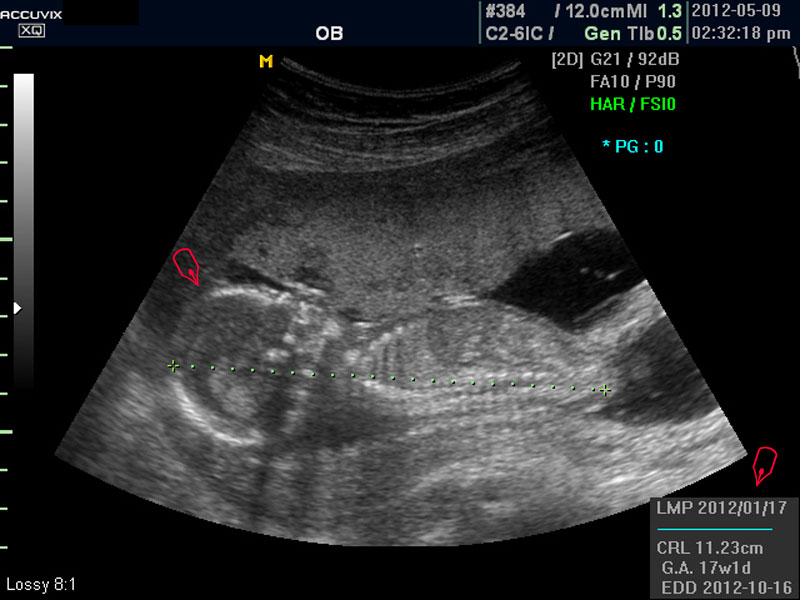

우선 초음파 사진에서 볼 것은 태아의 크기가 정상인가 하는 것입니다.

보통 태아의 발육은 머리부터 엉덩이까지의 크기인 CRL(Crown Rump Length의 약자)이 정상인가 하는 것과 태아의 두상 크기인 BPD(BiParietal Diameter의 약자)가 정상 범위에 들어 있는가 하는 것으로 판단합니다.

화면에서 좌측이 태아 머리 부분으로 빨간 펜으로 표시되어 있습니다.

초음파 상 태아의 머리가 좌측인가 우측인가 하는 것은 초음파 탐촉자의 위치를 어디에 두었느냐에 따라 다른 것 뿐으로 화면상 어디 위치하는 지는 중요하지 않습니다.

또한 이 시기는 태아의 크기가 양수에 비하여 아직 작기 때문에 자궁 내에서 하루에도 수십번 이리저리 방향을 바꾸는 시기이기 때문에 위치는 큰 의미가 없습니다.

태아의 머리가 정상 모양인가 크기는 정상인가 하는 것을 살펴 본 후에는 태아의 크기를 측정하고 가슴, 복부, 엉덩이 부분, 상하지 부분이 정상인가 하는 것을 살펴 봅니다.

대신 첫번째 사진에서 보는 것처럼 태아의 전체 모습 특히 태아의 등쪽이나 복벽의 이상은 없는지 신경관 결손 등으로 인한 종괴가 있지는 않은지 관찰하며 태아의 복벽이나 등쪽은 일직선으로 매끈하게 보이는 것이 정상입니다.

첫번째 사진에서는 하지 부분은 대퇴부만 일부 보이며 이는 태아가 다리를 구부리고 있고 팔도 이리저리 움직여 머리 위나 목 쪽으로 두는 경우가 많아서 한번에 전체 모습을 찍기가 어려운 경우가 많습니다.

모든 사진에서 우측 하단에는 기본적인 발육 정보가 기록되는데 세번째 사진에서 빨간 펜으로 표시한 부분이며 그 내용의 의미는 아래와 같습니다.

참고로 이런 측정 수치가 나타나는 양식이나 위치는 초음파 장비마다 다르지만 용어는 대체로 공통된 의학 용어를 사용하기 때문에 대동소이합니다.

1. LMP

Last Menstrual Period의 약자로 최종 월경일입니다. 이런 최종 월경일을 바탕으로 현재의 임신 주수와 초음파상 측정 지표들간에 얼마나 괴리 되어 있나 하는 것을 판단하는 것입니다.

2. CRL

위에 말한 태아 크기를 말하는 지표로 실제 수치가 표시됩니다.

3. GA

Gestational Age의 약자로 우리말로는 임신 주기라고 하며 CRL이나 BPD등을 기준으로 했을때 임신 몇주 며칠에 해당하는 지 나타낸 것입니다.

5.EDD

Estimated Due Date의 약자로 초음파 측정치를 바탕으로 산출한 출산 예정일입니다.